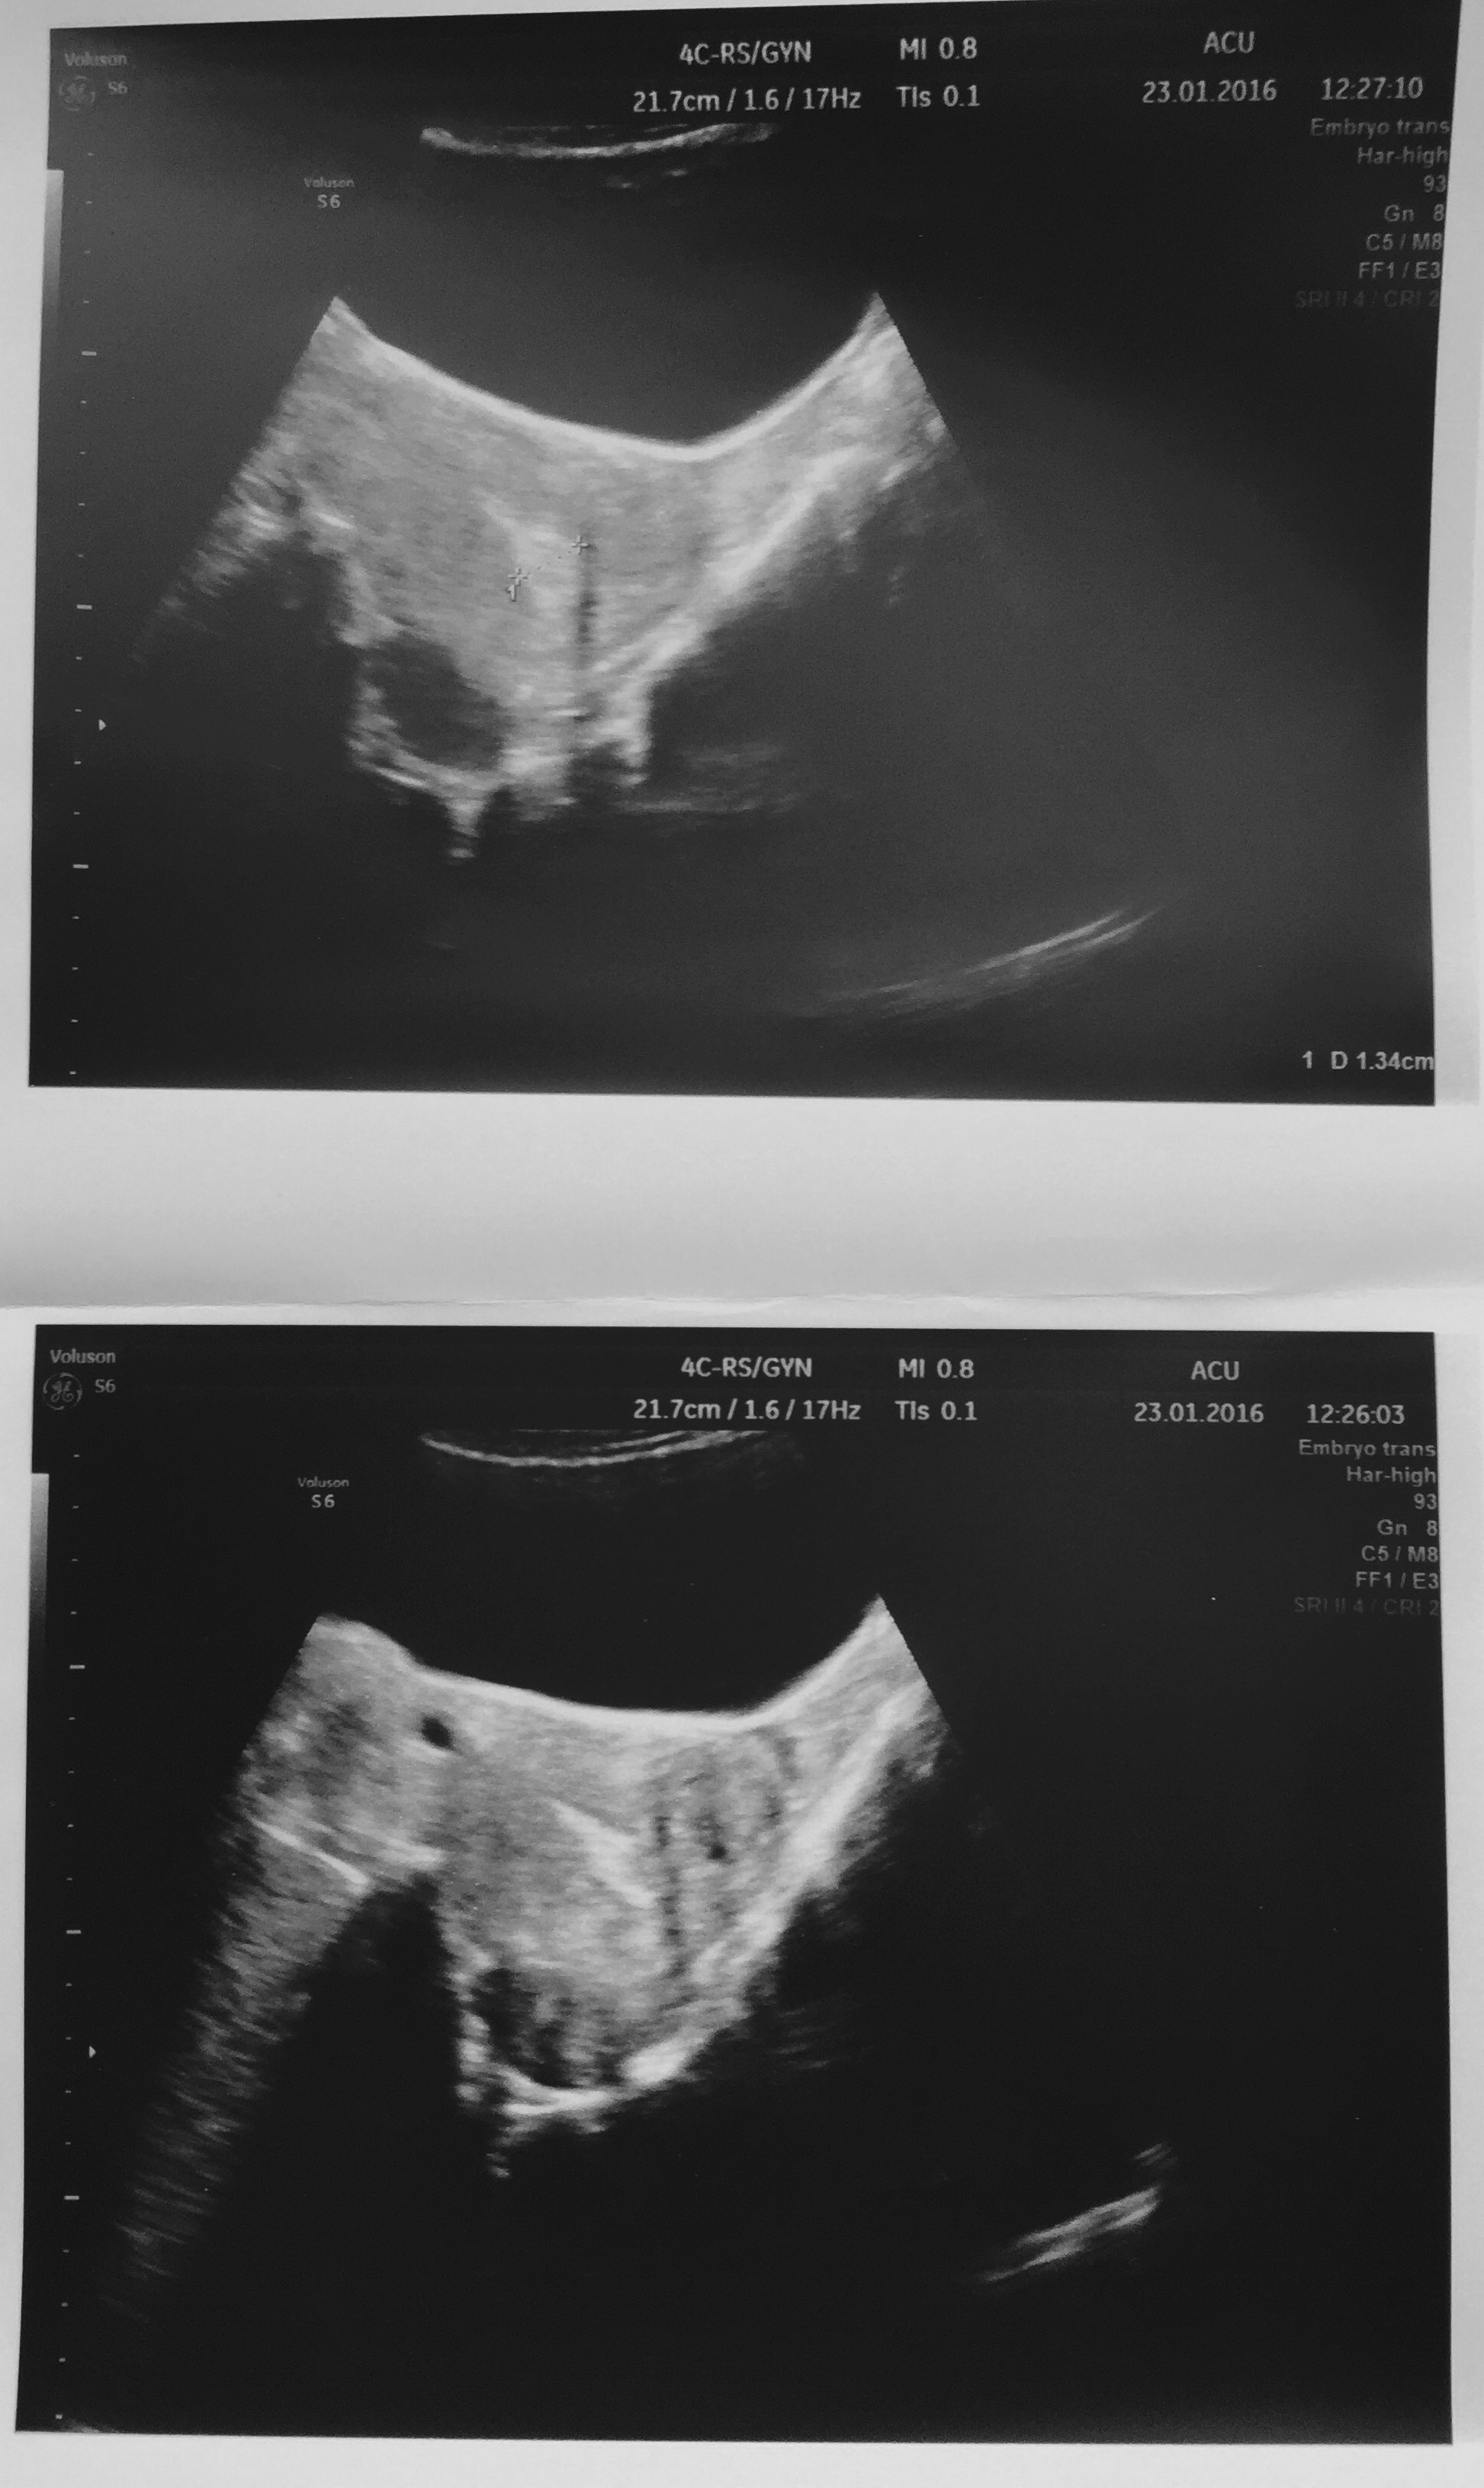

Our ‘secret’ is that for two years we have been trying to have a baby, without success. 24 months; approximately 25 doctor and hospital appointments and about 16 blood tests; cumulatively 4 weeks of nightly hormone injections administered by Hubby; other invasive tests and ‘endo scratches’; countless scans; fertility vitamins and folic acid tablets galore; follicle tracking; 3 egg collections; 3 nail-biting 24-hour waits for the fertilisation count; 20 precious oocytes; 8 viable embryos; 3 inordinately long waits to know the outcome; and buckets and buckets of tears.